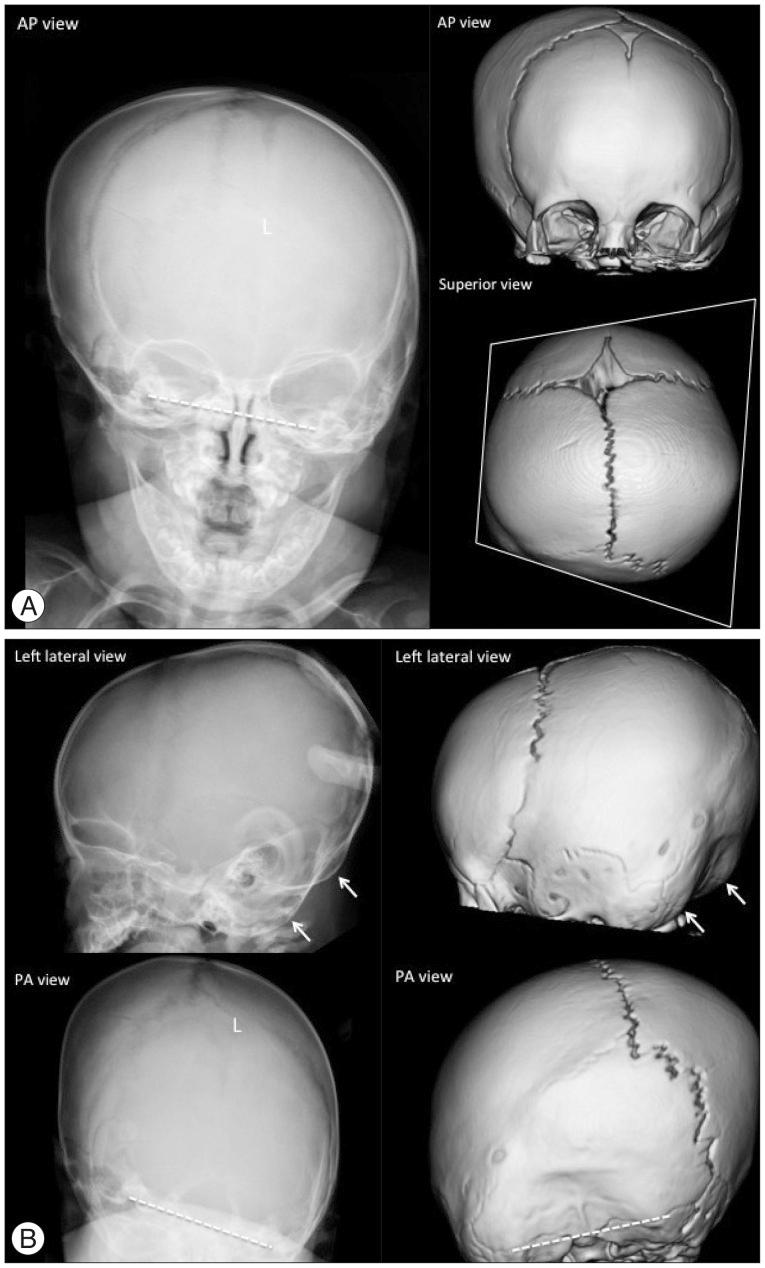

The purpose of this article is to review imaging findings and to discuss the optimal imaging methods for craniosynostosis. The discussion of imaging findings are focused on ultrasonography, plain radiography, magnetic resonance imaging and computed tomography with 3-dimensional reconstruction. We suggest a strategy for imaging work-up for the diagnosis, treatment planning and follow-up to minimize or avoid ionized radiation exposure to children by reviewing the current literature.

本文旨在回顾影像学表现,并讨论颅缝早闭的最佳影像学检查方法。影像学表现的讨论重点在于超声检查、X线平片、磁共振成像以及三维重建计算机断层扫描。通过回顾当前文献,我们提出了一种针对诊断、治疗规划及随访的影像学检查策略,以尽量减少或避免儿童受到电离辐射。